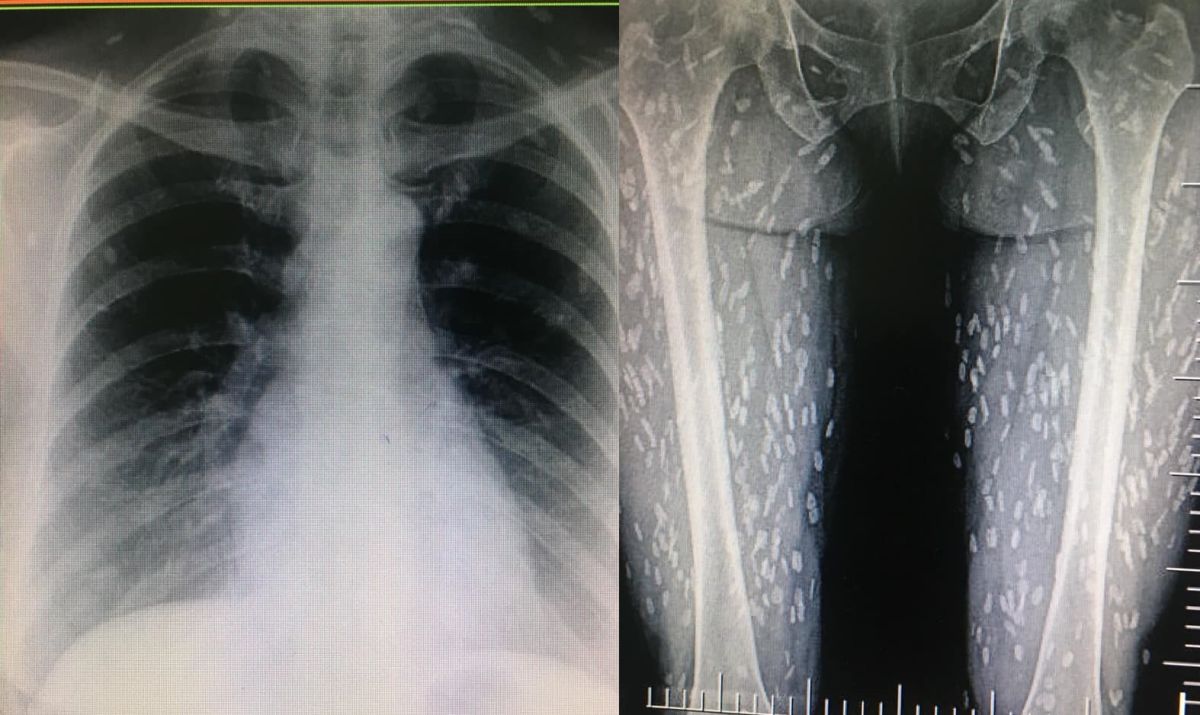

豬肉絕對不能生吃!泰國一名女子因為生吃豬肉,結果身體竟被數百隻絛蟲寄生。該名女子因為出現呼吸困難等症狀前往醫院檢查,一照X光片才發現絛蟲遍佈她的全身,讓人看了不寒而慄。

泰國Kwang Volemage網友在臉書分享一名女病患的X光照片,只見有大量一段一段的白色斑點遍布在患者的雙腿。據網友指出,這名女患者吃了生豬肉後,開始出現呼吸困難等症狀。經緊急檢查後才發現,原來身體已經被大量的豬肉絛蟲與幼體豬肉囊蟲寄生。

▲女子腿部已經被大量寄生蟲佔據。(圖/翻攝自Kwang Volemage臉書)